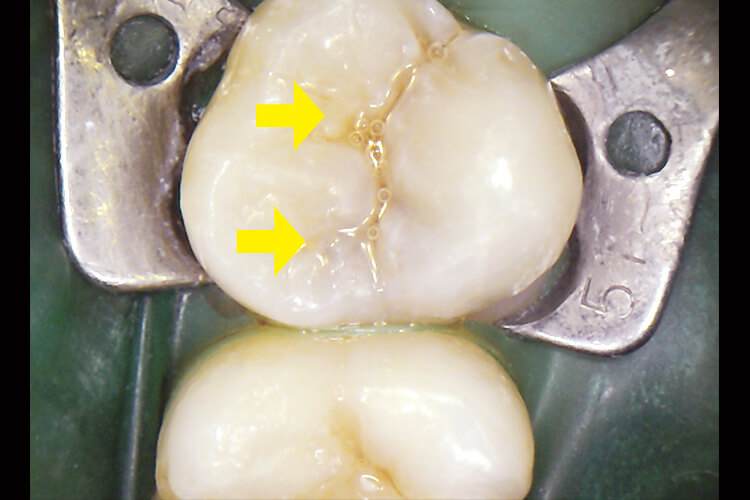

食辺圧入を主訴に来院された患者さんである(図14)。反対側も同様にCR修復が施術されており、自覚他覚症状も無くCRでの再修復を希望されていた。

機能咬頭の咬耗と辺縁隆線の破折が認められCRでの再修復は予後不良となる可能性が高いことを口腔内写真にて口頭で説明したが難色を示した。また、可能な限りメタル修復は避けたいとの訴えもあった。患者さんとの信頼関係が完成されるまでの初期の段階に多々あることである。

当院では患者さんに歯の価値観を共有してもらうためマイクロスコープを用いている。マイクロスコープは歯科医師・患者さん両方にとって見えないところまで見える(我々にとっては説明段階において痒いところまで手が届くといった感じ)確かなコミュニケーションツールであると言えよう。

図16 う蝕検知液には染色されてはいないが、歯質にマイクロクラックが認められる。患者さんとの情報共有に大きな影響を与えてくれる。

図17 遠心部にも同様にマイクロクラックが認められる(ラバーダム防湿+トッフルマイヤーリテーナーで完全防湿下)。